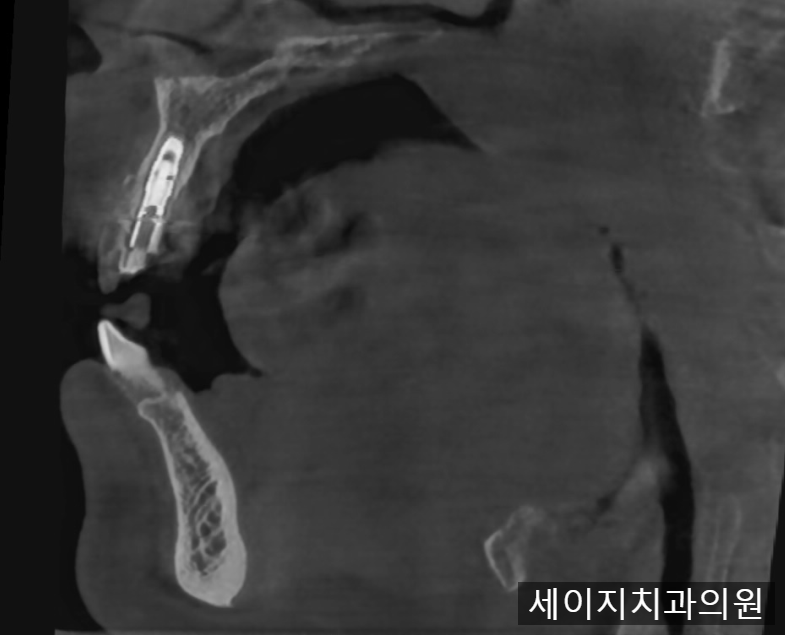

먼저 x-ray와 CT를 이용하여 정확한 뼈의 모습과 치아의 상태를 관찰하였습니다.

CT상으로는 입술에서 가까운 잇몸뼈의 흡수가 관찰되었습니다.

잇몸뼈의 소실이 크기에, 임플란트 진행시 심미적인 요소를 맞추기가 어려워 보였습니다. 때문에 환자분께 브릿지 치료도 하나의 옵션으로 권유드렸으나, 인접한 치아를 갈아내는 것에 대한 부담감이 크다고 이야기 해주셨습니다.

환자분과의 여러번의 상담을 통해서 심미적인 요소를 완성시키기 위해서는 앞니 임플란트 식립과 함께 CTG (Connective tissue graft) 라는 술식이 필요하다는 것을 말씀드렸고 환자분께서도 동의해주셨습니다.